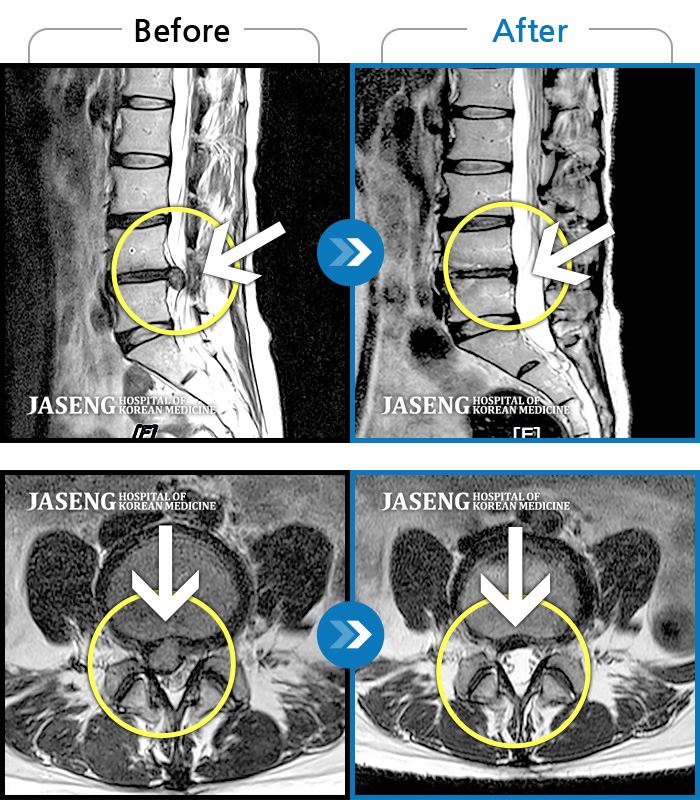

40대 초반 여성 환자인데요,, 처음 선생님 뵈었을 때에 1번,4,5번허리디스크 증상도 증상이지만,

본인 나이에 비해서 10~15년정도 퇴행이 많이 되어있어서 전체적으로 관리가 많이 필요하다고 설명해주셨구요,,

그당시 원장님진료실에서 보았던 저의 엠알아이사진이 아직도 생생히 기억이 납니다 ^^

뼈부분의 색이 왜저렇게 검냐고 여쭈어 보았더니, 말씀주신데로 "퇴행이"많이 되어서 그렇다고 설명해주시면서,,

그렇다고 당장 크게 머가 안좋거나 그런건 아니고,, 퇴행된 뼈자체를 새것으로 되돌릴수는 없지만,,

꾸준히 치료받으면서 관리만 잘한다면 건강한 뼈를 가진 사람과 동일하게 건강한 생활 충분히 가능할수 있다고,, 긍정적으로 말씀을 주셨어요...